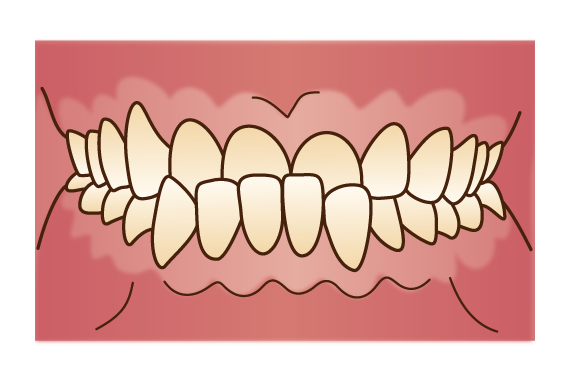

叢生

叢生は、歯並びがデコボコしたり歯と歯が重なり合ったりしている状態です。噛み合わせに問題が生じ、歯や歯茎、顎、消化管に大きな負担がかかります。また、歯をきれいに磨くことが難しいため、むし歯や歯周病によって歯を失うリスクが高まります。なお、八重歯も叢生の1種です。

叢生は、歯並びがデコボコしたり歯と歯が重なり合ったりしている状態です。噛み合わせに問題が生じ、歯や歯茎、顎、消化管に大きな負担がかかります。また、歯をきれいに磨くことが難しいため、むし歯や歯周病によって歯を失うリスクが高まります。なお、八重歯も叢生の1種です。